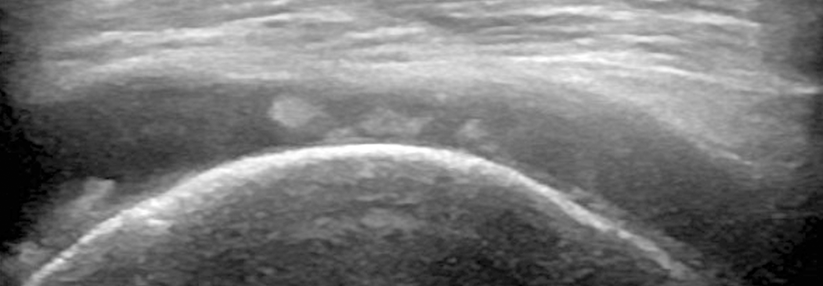

In der Bildgebung spielt der Röntgen-Thorax eine entscheidende Rolle, v.a. wenn es um die Halsrippe geht. Anhand einer überschießenden Kallusbildung oder Pseud­arthrose lassen sich stattgehabte Traumata bestätigen. Arterielle und venöse Schulterarmgefäße sind gut sonografisch zu beurteilen, jeweils in Ruhe und in Provokationshaltung (s. Kasten). Achten sollte man dabei auf Veränderung im Flussprofil sowie Stenosierungen, aneurysmatische Reaktionen und thrombotische Wandauflagerungen. Allerdings ist nicht jede provozierte Flussveränderung pathologisch, warnte die Expertin. Entscheidend für die Beurteilung sei die Zusammenschau von objektivem Gefäßbefund, Symptomatik und klinischer Reaktion während der Tests (z.B. Kribbeln, Kältegefühl, livide Verfärbung). Immer gehört auch eine neurologische Diagnostik (EMG/ENG) dazu, um z.B. ein isoliertes Karpaltunnel- oder Sulcus-ulnaris-Syndrom auszuschließen. Manchmal liegt Ersteres aber auch gleichzeitig zum TOS vor („double crush syndrome“). Die erweiterte Bildgebung umfasst MRT (u.a. zum Ausschluss von Tumoren) sowie spezielle angio­grafische Verfahren – Letztere sind nach Möglichkeit im Sitzen durchzuführen.

Gefäßcheck per Ultraschall

Durch gezielte Positionswechsel von Arm und Schultern kann man eine Scalenus-, Pectoralis- oder Kostoklavikular-Enge provozieren. Dazu zählen der ADSON-Test in maximaler Inspiration, der WRIGHT- und der EDEN-Test. In Provokation lassen sich dann per Duplexsono die Gefäße in diesem Bereich schallen. Für die exakte Ausführung der Tests ist es hilfreich, eine zweite Person hinzuzunehmen.